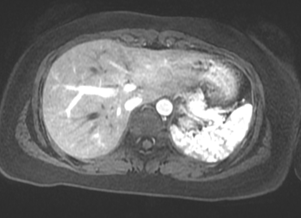

Making the models is a multi-step process; it begins when a doctor orders a medical imaging scan. The patient visits the radiology department for their scan, and X-ray technicians take a lot of images in sequence, moving across a section of the patient's body. For certain procedures, such as surgery to remove cancer, the Health Design Lab team can take those same imaging slices and create a digital 3D rendering. This is done by coloring in the desired areas on each 2D image, slice by slice, and using special software to turn this into a new three-dimensional file (a 3D rendering). This rendering is an exact 3D replica of the anatomy that is important in each patient’s case.

This digital rendering is then prepared into a format that a 3D printer can read, keeping into consideration things like the color of the material and the size of the model. Using the 3D information we send it, the printer builds up the model layer by layer. Now, a real organ--first fully digitized--exists as an almost exact plastic replica back in the real world. When printing different organs, various colored plastics can be used together to make a more complex model. If surgery is needed to remove a tumor, it can be printed using a different color than the organ it is growing in, so it is easier to see on the final model.

An example is currently on display in The Franklin Institute's Tech Studio: a model of hepatocellular carcinoma, a common liver tumor that a patient needed to have surgically removed. During the surgery, a section of the liver surrounding it also needs to be removed, along with other nearby organs blocking the surgeons' way. It is hard to appreciate this on a CT or MRI scan because the tumor in the liver is about three computer mouse scrolls away from a nearby organ, the gallbladder, that sits in front of it, so they don't appear on the 2D image. This causes confusion, as patients don't often understand why removing the gallbladder is necessary if the tumor is in the liver. However, when holding the 3D model in their hands, they see clearly that the neighboring organ also needs to come out to remove the tumor.